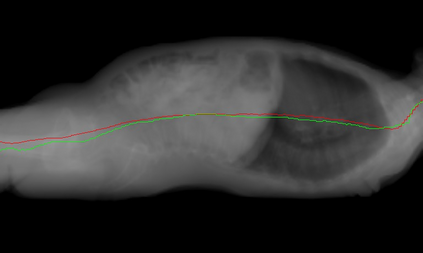

Despite recent developments in CT planning that enabled automation in patient positioning, time-consuming scout scans are still needed to compute dose profile and ensure the patient is properly positioned. In this paper, we present a novel method which eliminates the need for scout scans in CT lung cancer screening by estimating patient scan range, isocenter, and Water Equivalent Diameter (WED) from 3D camera images. We achieve this task by training an implicit generative model on over 60,000 CT scans and introduce a novel approach for updating the prediction using real-time scan data. We demonstrate the effectiveness of our method on a testing set of 110 pairs of depth data and CT scan, resulting in an average error of 5mm in estimating the isocenter, 13mm in determining the scan range, 10mm and 16mm in estimating the AP and lateral WED respectively. The relative WED error of our method is 4%, which is well within the International Electrotechnical Commission (IEC) acceptance criteria of 10%.